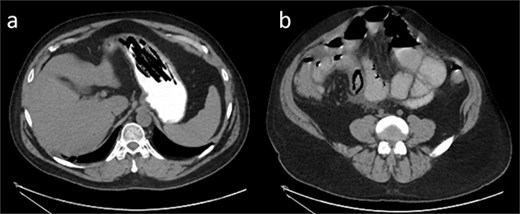

Labs were significant for leukocytosis to 13.4 and an isolated elevated alkaline phosphatase of 142. All other chemistries were stable. Initial read of non-contrast computed tomography (CT) abdomen/pelvis showed likely SBO with dilated loops of small bowel (Fig. 1). Image A shows a fluid-filled stomach. In image B, there is a “bowel-within-bowel” appearance concerning for intussusception as a lead point for SBO.

(a) Axial noncontrast CT of the abdomen demonstrating a nondescript, fluid-filled stomach. (b) Axial noncontrast CT reveals dilated loops of small bowel with classic “bowel within bowel” appearance of the small intestine, labeled with an arrow. This was thought to be the lead point for the suspected SBO.